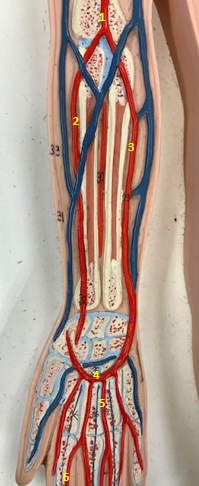

Right radial artery

Name #1

Supplies blood to hand wrist forearm

Function of right radial artery (1)

Right ulnar artery

Name #2

Supplies blood to fingers hand wrist forearm

Function of right ulnar artery (2)

Right brachial artery

Name #3

Supplies blood to arm forearm hand

Function of right brachial artery (3)

Right axillery artery

Name #4

Supplies blood to right armpit and upper limb

Function of right axillery artery (4)

Right brachial artery

Name #1

Right radial artery

Name #2

Right ulnar artery

Name #3